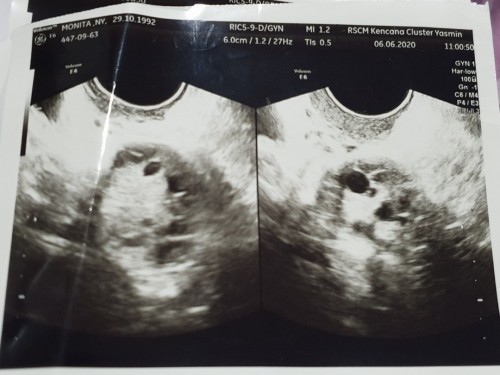

Haii semuanyaaa.... Ijinkan kami membagikan sepenggal kisah kami kepada teman teman semua. Perkenalkan Aku Mario dan Istriku Monita. Kami menikah November 2018. Setelah setengah tahun berlalu pernikahan kami, Kami mulai menantikan buah hati dapat hadir ditengah tengah kami. Kami mulai mencoba untuk konsultasi ke beberapa dokter namun belum ada hasil yang baik. Beberapa dokter yang kami coba datangi memberikan hadil diagnosa yang sama bahwa Istriku menderita PCOS Syndrom. Pcos Syndrome ini membuat telur telurnya sulit ntuk dibuahi padahal telur telur ini berjumlah banyak. Itulah yang membuat dia sulit untuk hamil dan membuatnya selama ini tidak memiliki siklus haid yang normal. 1,2n3 dokter kami coba. Berganti dokter, berganti rumah sakit sudah kami coba. Obat obatan yang disarankan teman ataupun keluarga pun sudah kami coba. Hingga sampai di 1 titik kami sudah lelah mencoba gunta ganti dokter, dan berkata, Tuhan jika memang Engkau belum mengijinkan kami menjadi orang tua, kami percaya waktuMu adalah waktu yang tepat. ******************************************** Hari berganti hari, dimana ad 1 moment yaitu kami ingin melakukan renovasi rumah. Saat proses renovasi rumah kami berlangsung, mama mertua ku berkata kepada kami, "rumah dulu beres renov, baru persiapan punya anak", saat itu posisinya kami sedang mencoba program ke dokter terakhir pilihan istri saya, dimana saya dan istri sudah sepakat jika tidak ada hasil juga maka kami akan stop untuk mencoba dokter dan membiarkan proses itu mengalir apa adanya hingga Tuhan percayakan buah hati kepada kami. Saat pertama kali istriku menemukan dokter ini, istriku memiliki keyakinan penuh untuk menggunakan dokter ini dan terlihat sangat excited dengan dokter ini. Dia adalah Dokter Tommy Gita Pratama, yang berpraktek di RSCM Kencana. Melewati 3 bulan program dengan dokter Gita, kami cukup excited dengan programnya. Mulai dari diet gula yang diprogramkan, mencoba olah raga, dan tentunya dengan program melalui obat. ******************************************** Sebenarnya yang sedang diprogram oleh dokter adalah membuat siklus haid istriku menjadi normal lagi sehingga telur yg diproduksi bisa matang pada waktunya. Jadi buat kalian yang bertanya tanya apakah program yang kami lakukan adalah inseminasi buatan atau Bayi Tabung. Itu bukan dua duanya. Kami masih dalam tahap mencoba kehamilan secara alami dengan bantuan obat yang membuat siklus haid istri menjadi normal. Jika kami melewati tahap ini dan belum berhasil, kami sudah sepakat untuk mencoba menggunakan program inseminasi buatan. ******************************************** Singkat cerita, Hari itu adalah minggu terakhir dari proses renovasi rumahku (Dimana proses renov ini berlangsung 1,5 bulan lamanya). Dipagi hari dihari sabtu yang cerah, istriku mengejutkan ku dengan tiba tiba menunjukan sebuah tespek yg menunjukan garis 2 dengan sangat sangatttt teballl..... Wawwwwww,,, amazingggg... God Is Good All The Time... Aku tertunduk menangis terharu ketika melihat tespek itu. Pagi itu kami berlutut berdua, berdoa. Mengucapkan syukur dan pujian kepada Tuhan kami Yesus. WaktuNya tidak pernah terlambattttt... Rumah sudah mau selesai Renov dengan biaya yang boleh Tuhan cukupkan. dan Tuhan memberikan berkatNya yang selanjutnya yaitu adanya Garis 2 pada tespek inii.. Hari itu kami langsung menuju ke rumah sakit untuk memeriksakan istri kepada dokter. Ketika diperiksa dan di USG, ternyata sedang terbentuk kantung rahim. Prediksi dokter saat itu usia kehamilan istriku memasuki 5 minggu. 2 minggu lagi kami disuru untuk menemui dokter. ********----------***********--------------******** Singkat cerita tibalah tanggal 12 Oktober 2020. Hari yang tak pernah kami sangka sebelumnya. Malam itu kami baru sampai dirumah setelah bekerja. Aku baru saja selesai masak dan menyiapkan makan malam dan istriku baru saja selesai mandi. Ketika malam itu kami baru saja akan makan, tiba tiba istriku merasakan ada yg mengalir melewati vagina nya seperti menstruasi. Dannnnnnn.... byuaaaarrrrrrr...... Darah segar mengalir dengan sangat banyaknyaaaa. Semakin dia disiram, semakin dia mengalirrrrr.... Disaat itu istriku yg panik dan histeris membuatku sempat terdiam mematung dihadapannya. Membuatku sejenak membeku tak dapat berfikir apa apa.. Sesaat kemudian segera aku mengambil handphone untuk mencari rumah sakit terdekat dari rumah yang memiliki dokter kandungan yang standby. Namun karena saat itu jam menunjukan pukul 22.00, maka sudah tidak ada dr obgyn yg standby. Setelah beberapa kali menelpon rumah sakit, akhirnya kami memutuskan untuk menuju ke rumah sakit XXXXXXX yang berlokasi di XXXXXXX karen lokasi itu yg terdekat dari rumah kami yaitu sekitar 40 menit dari parung panjang. Dengan mengucap doa, aku berangkat dengan hanya membawa dompet saja. Disepanjang jalan ke RS hatiku sangat kacau dan kalut, namun beberapa moment diperjalanan itu aku seperti mendengar seseorang berbicara dengan lembutnya padaku. "Marioo... Tenanglahhh. Fokus nyetir. Istri dan anakmu aman bersamaKu. Aku menjaga mereka" Seketika itu juga hatiku tenang dan damai. Berulang kali aku berucap pada istriku, tenang sayang, jangan panik, jangan menangis. Anak itu titipan Tuhan. Kalo Tuhan udah percayakan pada kita, pasti Tuhan jaga anak kita dengan baik. Jika belum waktuNya, berarti ini ujian iman kita biar kita naik tingkat. Ayo doa sama Tuhan, minta ketenangan hati biar gak tegang dan stress. Kalo ternyata "amin" calon anak kita masih ada, kasian dia karena ibunya stress.. *********-----------**********-----------********* Sesampainya di RS, jam sudah menunjukan pukul 23.00. Setelah mengurus administrasi, kami menuju UGD untuk ditindak lanjuti. Saat itu sudah tidak ada dokter obgyn yg jaga, namun akhirnya setelah tektokan dengan dokter kepala UGD, akhirnya ada bidan yang dapat dihubungi di Mess untuk dapat melakukan observasi kepada istri kami. Setelah bidan datang, kami menceritakan kejadian yg terjadi kepada bidan dan dokter kepala UGD. Segera setelah itu, bidan melakukan tindakan untuk melakukan pengecekan terhadap rahim istri saya. Ketika bidan itu memasangkan sebuah alat pada Ms. V istri saya, terlihat banyak sekali darah segar yang mengalir. Bidan itu dengan teliti membersihkan darah tersebut dengan kasa. Mungkin lebih dari 20 helai kasa habis untuk membersihkan darah tersebut. Dan ketika didetik terakhir ketika bidan hampir menyelesaikan tugasnya membersihkan darah,, Taaaaadaaaaaaaa!!!!!!!!!!!!!!!!!!!!!! Seonggok gumpalan darah besar megalir keluar dengan mudahnya diikuti seonggok kecil gumpalan berbentuk seperti janin (berbentuk seperti buah jeruk) keluar. Dan seketika itu juga berhentilah sudah pendarahan istri saya. Saya hanya mematung melihat gumpalan itu keluar saat diambil oleh bidan. Dan saya lihat diwajah bidan itu tersirat pesan serius yang akan segera disampaikannya kepada kami. Saya langsung menanyakan kepadanya, apakah gumpalan itu? Namun dia tidak langsung menjawab kemudian dia ijin pergi untuk bertemu dokter kepada UGD terlebih dahulu. Didalam ruang UGD, aku hanya bisa pasrahh. Aku melihat raut kesedihan yang belum pernah aku lihat sebelumnya selama aku mengenal istriku. Tanpa tersadar, air mataku menetes membasahi pipiku. Tidak lama kemudian bidan kembalii.. Dan aku pun menanyakan diagnosa dia sebagai bidan yang sudah berpengalaman menangani orang yang hamil dan melahirkan selama ini. Dengan dimulai dengan perkataaan "Bapak Ibu, mohon maaf mungkin yang saya sampaikan ini tidak sesuai dengan harapan kalian" Berdasarkan pengalaman saya, dan melihat 2 gumpalan ini, diagnosa saya adalah istri bapak telah mengalami Abortus (keguguran) . Bagaikan petir menyambar disiang bolong, hatiku rasanya hancur seketika, dan istriku menangis dalam diamnya namun aku tau hatinyalah yang paling hancur. "Namun ini hanya diagnosa ya pak, bu, karena saya tidak bisa melakukan usg" namun kemungkinan jika di USG hasilnya tetap sama. Hanya perlu dipastikan apakah ini abortus sebagian atau abortus seluruhnya. Jika sebagian maka harus segera dilakukan tindakan kuret agar tidak membahayakan rahim istri bapak. Ketika itu hati kecilku seperti ada yang berkata "tenang mario, Aku ada bersamamu". Seketika itu pula hatiku merasakan damai sejahtera dan ketenangan. Aku berbisik pada istriku, "Yank, anak itu titipan Tuhan" jika memang ini adalah hadiah untuk kita, pasti Tuhan jaga didalam kandunganmu. Ternyata istriku merasakan hal yang sama "batinnya mengatakan janin kami masih ada didalam". Hari itu bidan dan dokter kepala UGD menyarankan kami untuk menginap untuk besok pagi dapat langsung dilakukan observasi dan tindakan oleh dokter Obgyn disana. Namun saat itu juga aku menolak itu dan mengatakan, aku akan membawa istriku keluar dan malam ini juga aku akan bawa istriku ke RSCM untuk besok dapat dicek oleh dokter yang menangani istriku. Malam itu aku menelpon kaka iparku untuk meminta pendapatnya. Dan hasilnya sama. Dia setuju untuk aku membawa istriku ke RSCm untuk diobservasi disana dan ditangani oleh dokter yang memang mengerti kondisi istriku. Malam itu kami pulang dulu kerumah untuk mengambil KTP, dan beberapa baju salin berjaga jaga jika harus di opname di RS. Sesampainya dirumah istriku langsung menangis sejadi jadinya dan terkulai dilantai. Malam itu ada yang menguatkan hatiku dan mengatakan "Tenang.... Tegakkan hatimu, hibur istrimu, Aku besertamu" Aku memeluk istriku dan mengatakan, Tuhan Yesus baik. Apapun yang terjadi, Tuham Yesus baik. Jangan pernah kecewa pada Tuhan.. Tuhan yang memberi, Tuhan yang mengambil. Terpujilah nama Tuhan. Koko percaya Anak kita dijaga oleh Tuhan didalam sana, dan dia masih ada bersama kita. Itu iman Koko saat ini. Tuhan ada saat ini bersama kita, rasakan hadiratNya. Saat itu jam menunjukan pukul 00.30 dini hari. Namun tidak ada perasaan ngantuk maupun lapar yang aku rasakan padahal kami belum makan sesuap pun malam itu. Kami langsung bergegas ke RSCM. Namun saat itu di RSCM tidak ada dokter spesialis obgyn yang standby dan kami masuk ke klinik 24jam disana. Disana ada dokter internis yang betugas jaga malam itu. Setelah dilakukan cek tensi, dikatakan bahwa semua normal. Dan saat dicek malam itu, pendarahan istriku sudah berhenti. Namun berdasarkan apa yang kami ceritakan dan diagnosa di RS sebelumnya, dokter ini memikirkan hal yang sama dengan diagnosa di RS sebelumnya, hanya bedanya dokter internis ini hanya berpendapat setelah mendengar cerita kami tanpa melakukan pengecekan rahim istri saya karena memang itu bukan bidangnya. Saat itu kami tidak putus harapan, dan karena istri saya merupakan pasien lama disitu, kami minta bantuan agar ada dokter obgyn yang bisa datang untuk mengecek istri saya. Kami berharap jika memang masi bisa tertolong, maka waktu emas itu tidak berlalu sia sia karena kami membuang waktu yang berharga itu untuk menantikan dokter Gita praktek yang saat itu beliau baru buka praktek jam 10.00 pagi. Setelah berdebat cukup panjang dengan dokter dan petugas di klinik 24jam, tiba2 saja salah seorang perawat mengatakan, "Jika bapak ibu mau, bapak ibu bisa menuju ke UGD RSCM pusat yang berada disebelah rumah sakit ini, disana ada dokter obgyn yang saat ini sedang bertugas". Tanpa buang waktu kami lansung menuju ke RSCM pusat. Saat itu waktu menunjukan pukul 03.00 subuh. Sesampainya di RSCM pusat, istriku langsung ditangani oleh petugas dan dibawa menggunakan kursi roda sesaat kami melapor bahwa istri telah mengalami pendarahan hebat malam itu. Sembari istri dibawa ke ruang khusus tindakan pasien hamil, aku mengurus administrasi. Setelah selesai mengurus administrasi tersebut, aku langsung menuju ke lantai dimana istriku berada. Saat aku sampai, aku tidak diijinkan masuk, dan saat itu sudah ada 3 dokter yang sedang menangani istriku. Didalam aku mendengar bahwa istriku sedang menceritakan kronologi cerita sambil menangis. Saat itu dokter obgyn yang bertugas sedang melakukan operasi persalinan, sehingga yang menangani istriku adalah dokter residen dan dokter Koas. Namun saat aku berada diruangan, istriku sedang bersama dokter Koas dan dokter Residen sedang tidak ditempat. Mendengar cerita dari istriku, dokter Koas ini penasaran dan karena keingin tahuan dan rasa penasaran yang tinggi, akhirnya dia melakukan USG perut kepada istriku. Dan apa yang terjadiii....... Tiba2 saja ketika dia sedang melakukan USG, sang dokter Koas tersentak kaget dan mengatakan, "Sepertinya saya mendengar suara detak Jantung" Dokter koas ini menggeser geser alat USG tersebut ke perut istriku bagian lain, dan benarrrrrrrrr,,, suara itu makin jelas. Saking paniknya dia, dia segera memanggil seniornya yaitu dokter Residen. ******************************************** Namun saat itu aku tidak mendengar percakakan mereka karena aku sedang menelpon mamahku untuk meminta doa darinya. ****************************************** Aku ingat jelas nama dokter Malaikat itu. Dialah dokter Andro... Dokter Andro melakukan USG transvaginal untuk memeriksa kandungan istriku dengan detail. Aku pun dipanggil kedalam untuk menyaksikan proses USG itu. Dengan hati berdebarrr dan penuh harapan.. Dannnnnnnnnnnnnn................... Diaaaaaa adaaaa.... Anakkkuuuu masiihhhh adaaaaaaaaaa... Dann dia sudah berbentukkk janinnnn... Dokter Andro dengan wajah yang gembira mengatakan, kandungan ibu tidak apa apa, kantong rahim ibu masih utuh, dan kalian bisa lihat, janin kalian tidak apa apa. Detak jantungnya sangat baik. Dan lihatlah apa yang sedang ia lakukan. Dia sedang menghentak hentakan kakinya didalam dan bergoyang goyang. Bekas pendarahan memang masih ada, namun ini bukan berasal dari dalam rahim maupun janin kalian........ Janin ini masih ada bersama dengan kaliannn..... Dan untuk 2 onggokan yang kalian perlihatkan ini, saya juga tidak tau apakah ini darah atau apa. Biarlah itu menjadi rahasia Tuhan. Saat itu lah ketika aku mendengar detak jantung calon anakkku,, air mata bahagiaku tidak berhenti menetes. "Yesss Jesuss,, Engkau ada" "Engkau sungguh ada bersama dengan kami... Engkau ada disini, memperlihatkan bahwa Engkau sungguh ada dan hadir dalam situasi ini. Engkau yang menenangkan hati kami dan berkata jangan khawatir,Percayalah Aku ada" Tidak ada kata yang mampu kami ucapkan selain Trima kasih Yesus.. Hari itu aku mengalami perjumpaan pribadi yang begitu Indah dengan Tuhan. Bagaimana Tuhan berbicara sebagai Pribadi Bapa kepada AnakNya dengan mengatakan, "Jangan takutt,, sebab Aku besertamu" Malam itu kami berdua pulang dengan Hati yang bersuka cita. Bukan saja bersuka cita karena anak yang kami dambakan masih ada bersama dengan kami, tapi terlebih dari itu, Malam itu kami berdua melihat bahwa Yesus berjalan bersama dengan kami, Ia menangis bersama kami dan Dia memeluk kami memberikan ketenangan kepada kami dan SuaraNya jelas terdengar direlung hati kami yang paling dalam "Tenanglah Anakku, Aku bersamaMu. Percayalah, anak kalian aman bersamaKu didalam kandungan istrimu, Sebab Akulah Tuhan yang menjaganya" ********************End******************** Akhir Kata, saya ingin berterima kasih kepada Dokter Dokter Malaikat di RSCM Pusat,, terkhusus Dokter Andro yang sudah menolong istri saya melewati sulitnya malam 12 Oktober 2020 dan mengembalikan kebahagiaan kami kembali. Semoga Tuhan Memberkati Dokter Andro bisa lulus menjadi Spesialist Obgyn dan dapat menjadi dokter Obgyn yang memberkati banyak pasangan. Walaupun masih Dokter Residen namun Dokter Andro menangani istri saya dengan sangat profesional dan sangat Sigappp.. Kepada Dokter Herbert Situmorang, kami sangat berterima kasih kepada dokter Residen dari dokter Herbert yang sudah membantu kami melewati sulitnya malam itu. Terima kasih banyak juga kami berdua ucapkan kepada Dokter Tommy Gita Pratama, yaitu dokter yang kami percayakan untuk membantu program kehamilan istri saya sehingga saat ini istri saya dapat hamil dan saat ini usia kandungannya menginjak 11 Weeks.. *****Nama Rumah sakit dan Dokter tidak kami samarkan dan sengaja kami sebutkan, karena ucapan terima kasih yang tidak terhingga kami ucapkan kepada RSCM dan Dokter yang menangani Istri saya****** Semoga cerita ini menjadi berkat bagi siapapun dan menjadi kekuatan bagi kita semua. Saya tutup dengan sebuah ayat yang sangat memberkati saya: "Dan ketekunan menimbulkan tahan uji dan tahan uji menimbulkan pengharapan. Dan pengharapan tidak mengecewakan, karena kasih Allah telah dicurahkan di dalam hati kita oleh Roh Kudus yang telah dikaruniakan kepada kita" -Roma 5: 4-5- *-*-*-*-*-*-*-*-*-*-*-*-*-*-**-*-*-*-*-*-* "Sebab Engkaulah yang membentuk buah pinggangku, menenun aku dalam kandungan ibuku. Aku bersyukur kepada-Mu oleh karena kejadianku dahsyat dan ajaib; ajaib apa yang Kaubuat, dan jiwaku benar-benar menyadarinya. Tulang-tulangku tidak terlindung bagi-Mu, ketika aku dijadikan di tempat yang tersembunyi, dan aku direkam di bagian-bagian bumi yang paling bawah; mata-Mu melihat selagi aku bakal anak, dan dalam kitab-Mu semuanya tertulis hari-hari yang akan dibentuk, sebelum ada satu pun dari padanya. Dan bagiku, betapa sulitnya pikiran-Mu, ya Allah! Betapa besar jumlahnya! Jika aku mau menghitungnya, itu lebih banyak dari pada pasir. Apabila aku berhenti, masih saja aku bersama-sama Engkau" -Mazmur 139:13-18- Tuhan Memberkatii kita semuaa,, Aminn........ #KesehatanMentalTAP